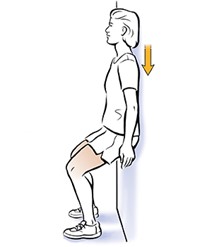

- مینی اسکوات(چمباته زدن)( تصویرشماره ۱۲) : نوع دیگری از تمرین است که می تواند عضلات چهار سر ران و عضلات بزرگ جلوی ران را تقویت کند.

- با پشت خود به سمت دیوار بایستید، در حالی که شانهها و سر خود را به دیوار تکیه داده باشید.

- پاهای شما باید به اندازه عرض شانه باز باشند و حدود ۳۰ سانتی متر از دیوار فاصله داشته باشند.

- زانوها را کمی خم کرده و باسن را به سمت زمین بیاورید.

- زمانی که میزان خمیدگی به زاویه ۱۵ درجه رسید در همان حالت بمانید.

- به مدت ۱۰ ثانیه در این حالت بمانید، سپس بدن را به آرامی به حالت اولیه برگردانید در حالی که پشت و شانههای شما همچنان به دیوار چسبیده باشد.

- این حرکت را بصورت ۲ ست و در هر ست ۸ الی ۱۰ مرتبه تکرار کنید. ما بین ستها میتوانید ۳۰ ثانیه الی ۱ دقیقه استراحت کنید.

- توجه داشته باشید که تکیه دادن پشت و شانهها به دیوار حین انجام دادن این حرکت، نکتهی بسیار مهمی است چرا که فشار روی زانوها را کاهش میدهد.

(تصویرشماره۱۲)